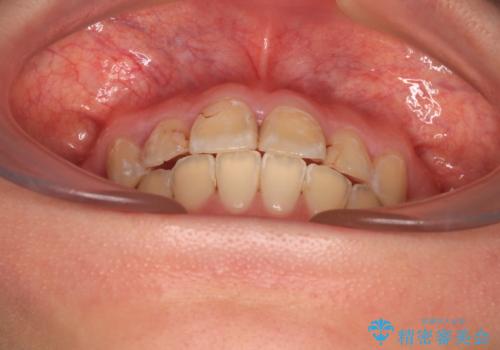

- 上の前歯の出っ歯とでこぼこの歯並びを気にして来院された患者様です。

上下顎歯列ともに前方に突出していましたが、上顎歯列がより前方位にあったため、上顎左右は第1小臼歯を、下顎左右は第二小臼歯を抜歯することとしました。

目立たないワイヤー装置にて抜歯矯正を行うこととしました。